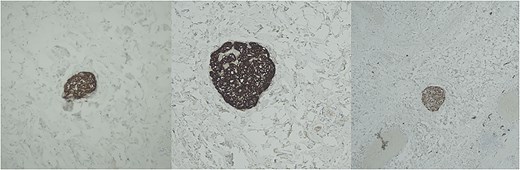

Histopathological analysis of the gallbladder demonstrated follicular cholecystitis along with an incidental paraganglioma (Fig. 4). This lesion showed positivity with CD56, synaptophysin, and chromogranin staining with admixed S100-positive sustentacular cells (Fig. 5). Keratin was negative.

Immunohistochemistry for chromogranin (left), synaptophysin (middle), and S-100 (right).